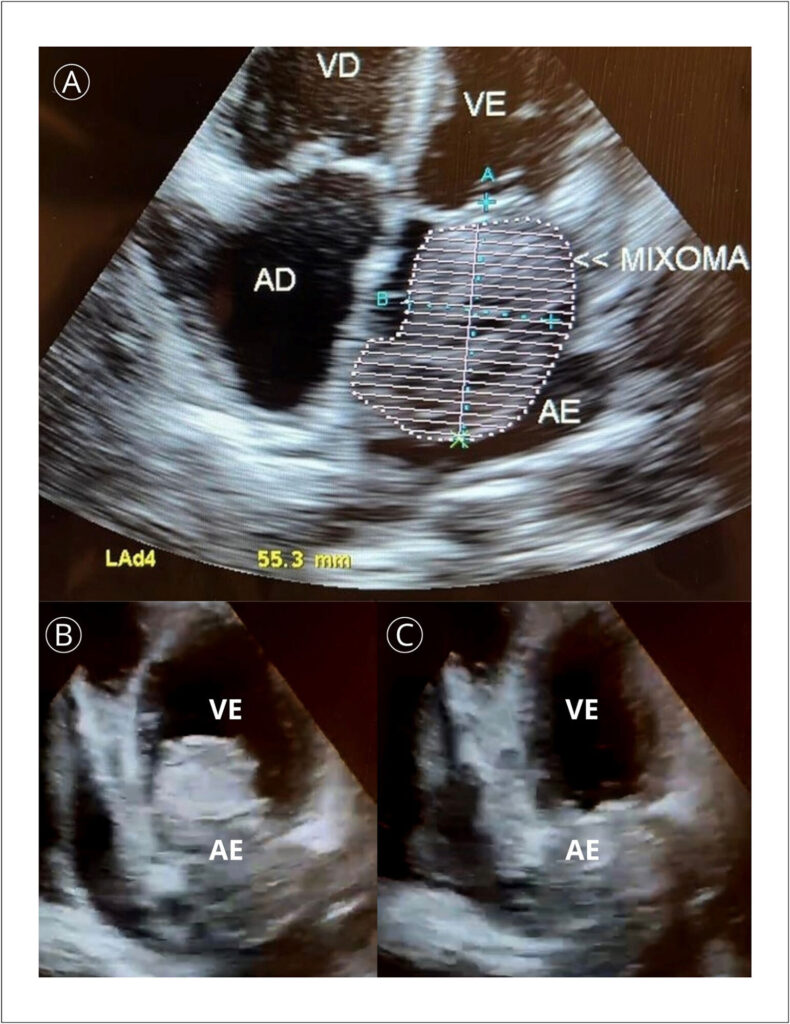

Mixoma Atrial em Paciente Adulto Jovem do Sexo Masculino: Relato de Caso e Revisão de Literatura

Tumores cardíacos são encontrados em 0,001 a 0,3% das autópsias, sendo o mixoma a neoplasia cardíaca mais comum. Aproximadamente 70% surgem no átrio esquerdo próximo ao forame oval e são pedunculados. Seu pedúnculo pode ser curto, limitando sua movimentação, ou pode ser longo, permitindo que o tumor entre e saia do átrio durante o ciclo cardíaco.,

O quadro clínico depende de tamanho, mobilidade e localização. A sintomatologia clássica é relacionada à tríade de Goodwin, que inclui sintomas sistêmicos inespecíficos, embolismo e obstrução intracardíaca. Dentre os sintomas sistêmicos estão dispneia, ortopneia, dispneia paroxística noturna, edema pulmonar, tosse, hemoptise, edema e fadiga, decorrentes principalmente do caráter obstrutivo da neoplasia.,